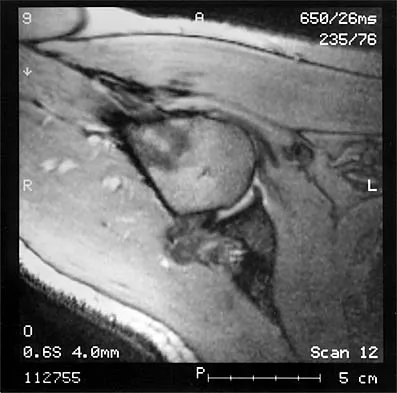

Figure 37 shows the T2-weighted MRI scan of the hip joint. What structure is labeled A?

An 18-month-old boy with obstetric brachial plexus palsy is being evaluated for limited right shoulder motion. Physical therapy for the past 6 months has failed to result in improvement of the contracture. Which of the following studies is necessary prior to any shoulder reconstruction?